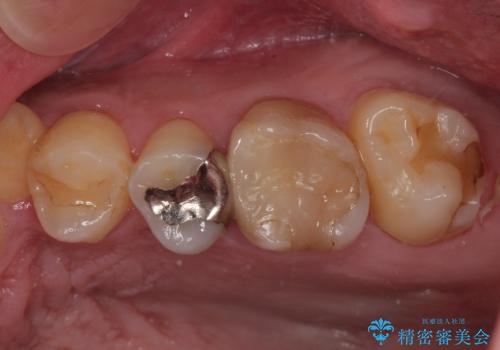

銀歯の下の虫歯を治したい オールセラミッククラウン・セラミックインレー修復